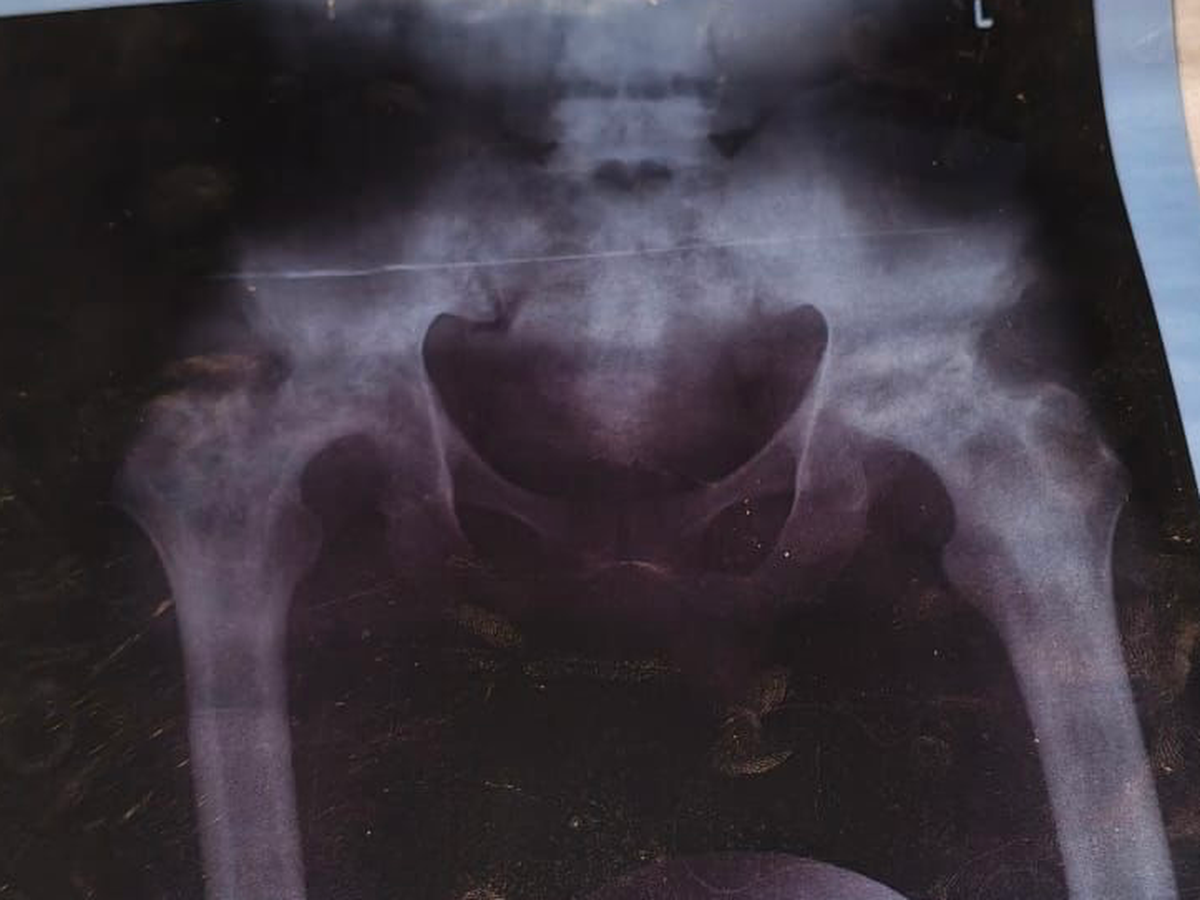

Benjamin Asimeng, a 25 year old determined young man and one of four children raised by a hardworking single mother. For the past two years, Benjamin has been living with persistent and worsening pain in his hips. After finally seeking medical attention, he was diagnosed with avascular necrosis — a serious condition that causes the bone tissue in the hip to die due to lack of blood supply.

Recently, with the help of generous friends, Benjamin was able to visit St. Joseph’s Hospital in Koforidua, a facility well known for its specialized care in bone-related conditions. The news was devastating ,his condition has significantly deteriorated, and he now urgently needs surgery on both hips to prevent further damage and permanent disability.

Each hip surgery costs 72,000 Ghana cedis, bringing the total needed to 144,000 Ghana cedis. This life-changing procedure will relieve his pain, restore his mobility, and give him a chance to rebuild his future.